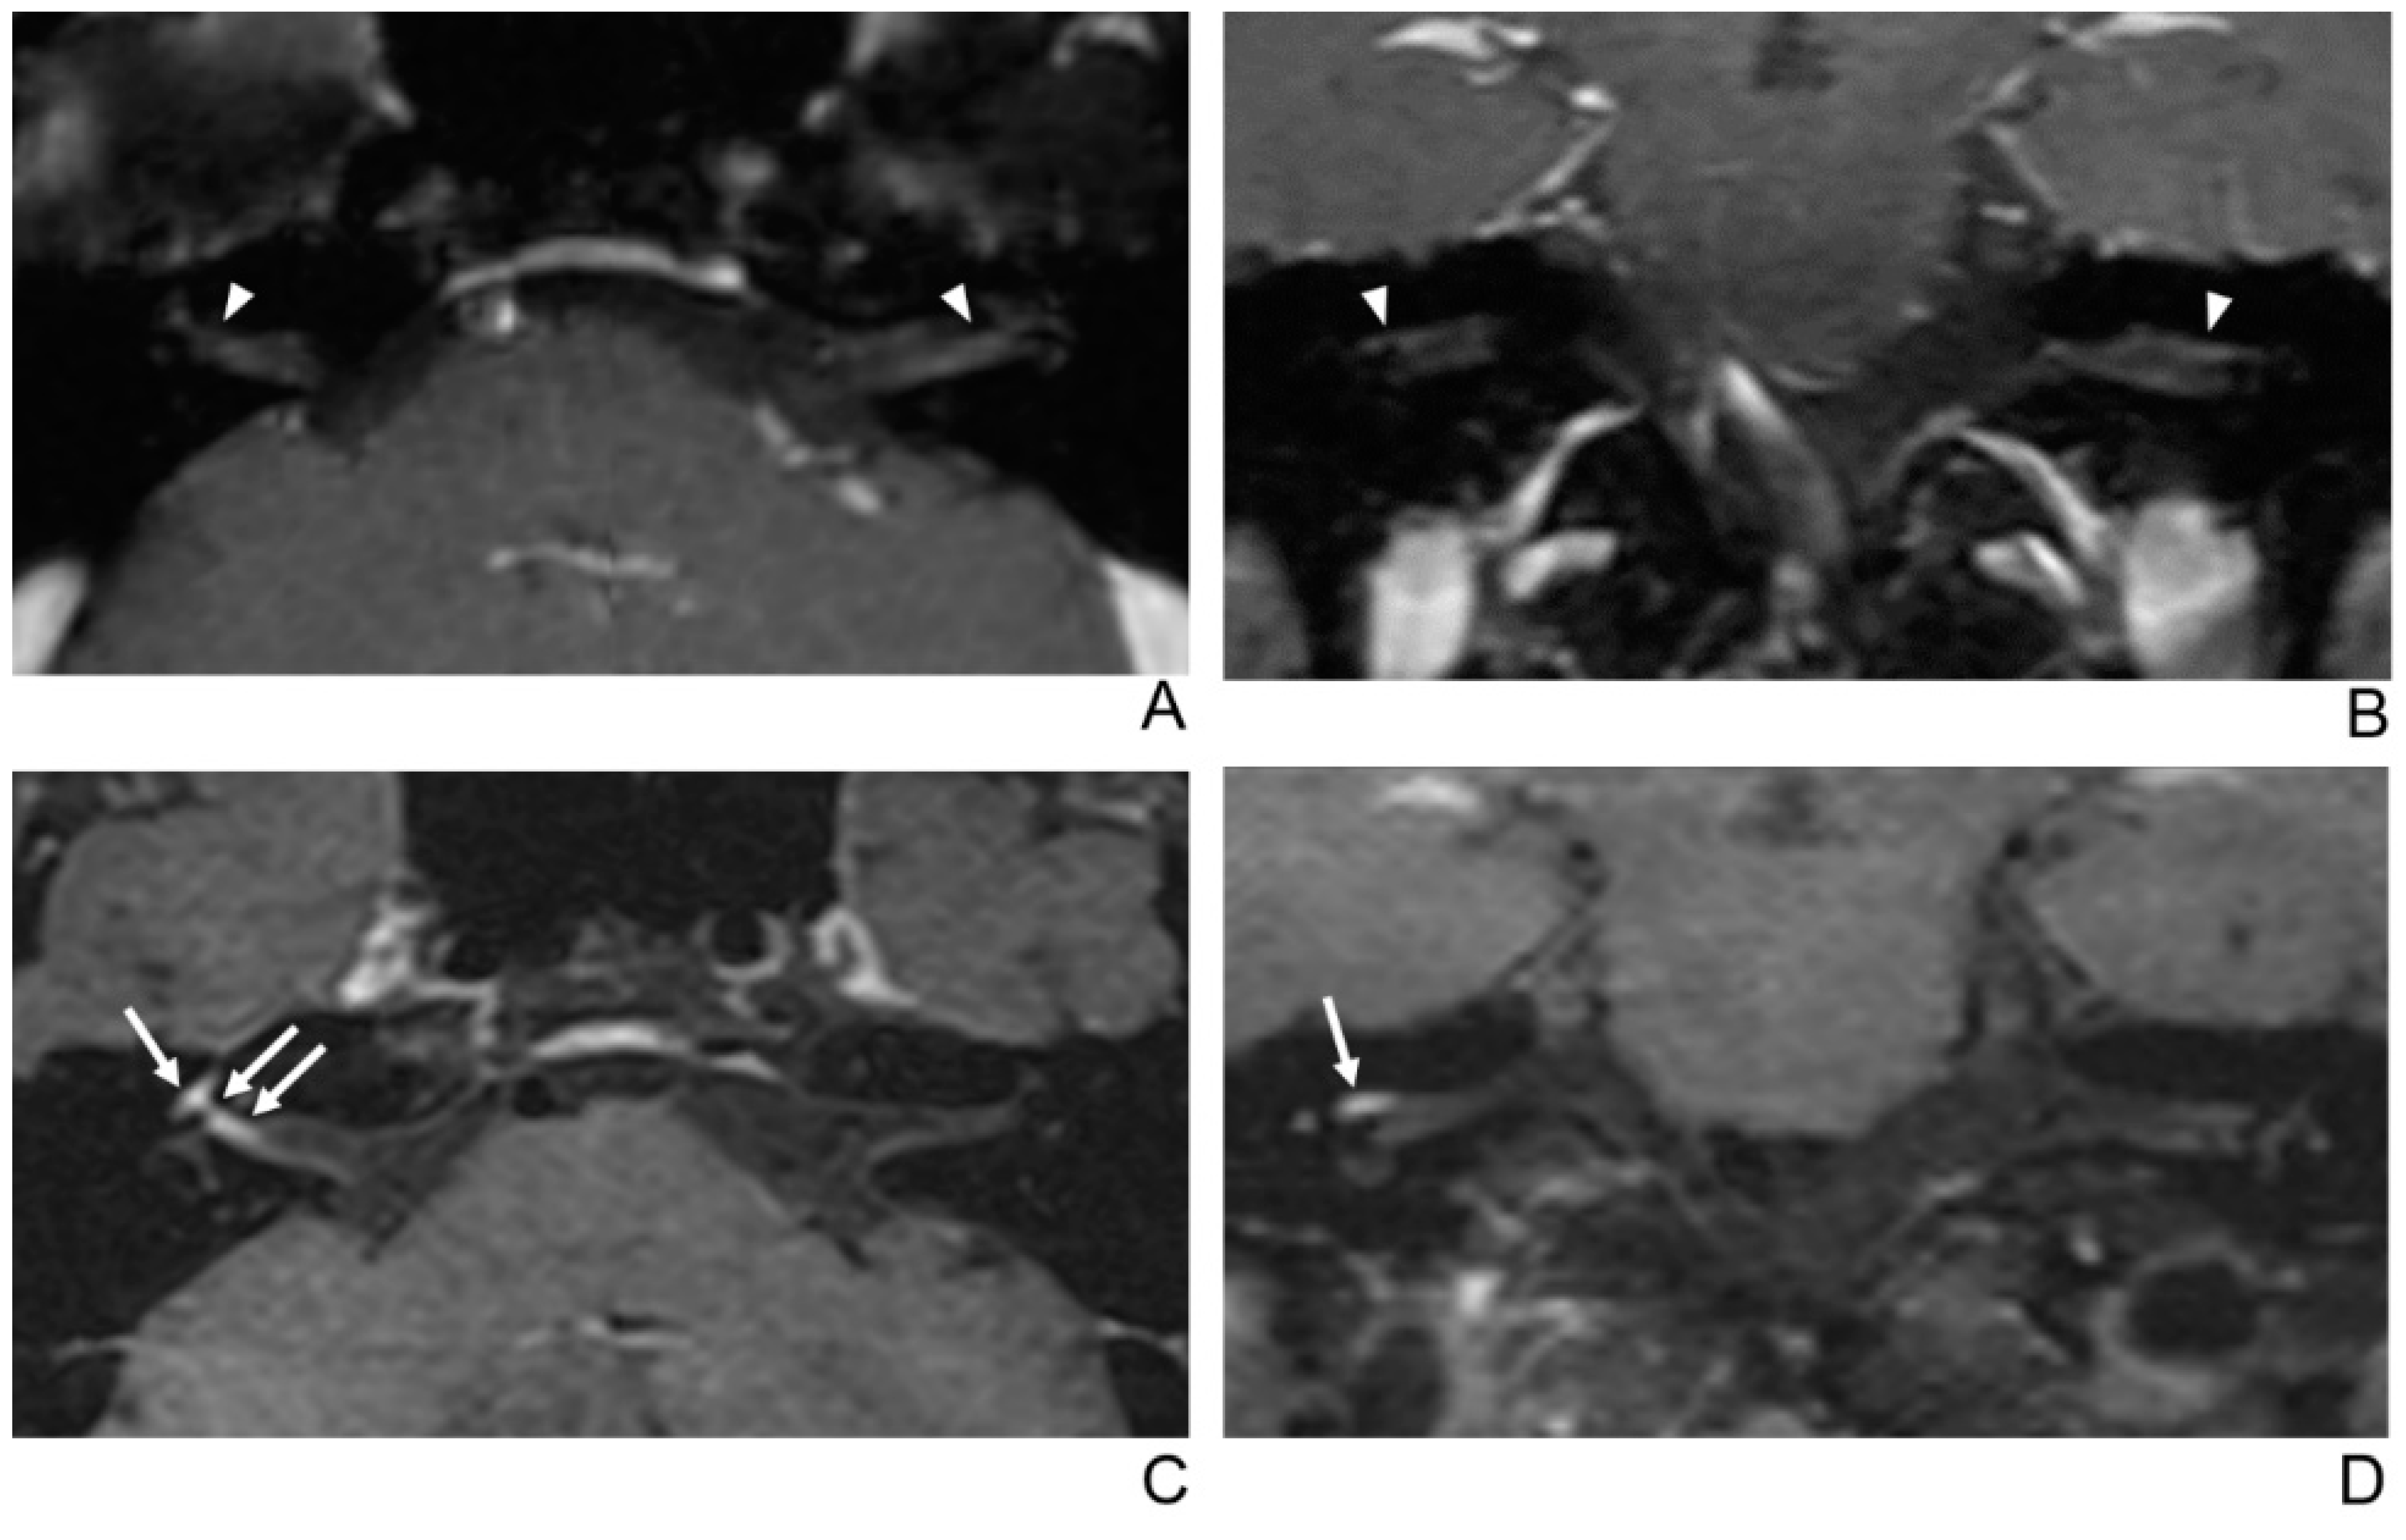

Figure 4.

A 56-year-old female patient with right facial neuritis. (A–D) Paired axial and coronal CE-GRE (A,B) and T1 BB-FSE (C,D) images of the same patient. In the axial (A) and coronal (B) CE-GRE images, no definite asymmetric enhancement was demonstrated in the bilateral facial nerves (arrowheads); thus, it was evaluated by reviewers 1 and 2 as normal facial nerves (false negative). In contrast, the right facial nerve shows asymmetric intense enhancement in the canalicular, labyrinthine, and anterior genu segments in the T1 BB-FSE axial (C) and coronal (D) images (arrows); thus, the two reviewers interpreted the enhancement as right facial neuritis (true positive; 2, diagnostic confidence; 3, 2, and 3, visual grades for CE in the canalicular, labyrinthine, and anterior genu segments, respectively).